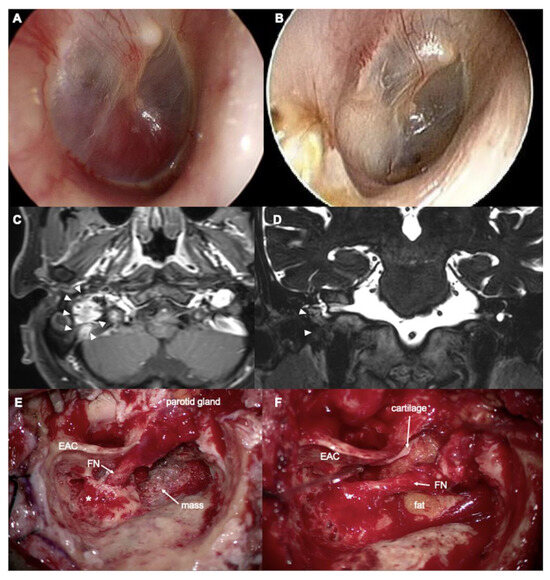

A 61-year-old man presented with right-sided hearing loss, accompanied by pulsatile tinnitus during head movement and a sensation of ear fullness for two years. Tympanic endoscopy revealed a pulsatile reddish mass behind the right tympanic membrane (Figure 1A). Temporal bone computed tomography (CT) and magnetic resonance imaging (MRI) (Figure 1C,D) demonstrated a 2.3 cm well-enhancing, hypervascular soft tissue mass in the middle ear and jugular foramen, highly suggestive of a glomus jugulare and tympanicum. The inferomedial bony wall of the EAC was eroded. The air conduction pure tone average in the right ear was 45 dB HL, with an ABG of 4 dB HL. No facial palsy was noted preoperatively. Preoperative embolization of the right occipital artery and postauricular artery was performed.

Surgery was performed using a modified IFTA technique, preserving the posterior EAC. After a complete canal wall-up mastoidectomy and posterior tympanotomy, the facial recess was widened inferiorly by removing the inferior portion of the bony EAC. A vascular mass was identified in the hypotympanum and jugular fossa. The facial nerve was skeletonized and rerouted anteriorly from the pyramidal segment to the parotid segment (short rerouting) (Figure 1E). The entire mass was removed from the hypotympanum, mastoid cavity, and jugular fossa. The tumor was adhered to the jugular bulb without internal invasion. The adhered mass was carefully removed, and bleeding from the jugular bulb was controlled using Gelfoam. The inferior EAC bony defect was covered by cartilage and supported by fat obliteration of the mastoid cavity (Figure 1F). Postoperative air conduction PTA was 44 dB HL with an ABG of 0 dB at the 3-year follow-up. The latest follow-up MRI, conducted 3.5 years after surgery, showed no recurrence of the tumor. The patient had an intact right tympanic membrane and EAC (Figure 1B). Figure 2 shows an illustration of the surgical process.

Figure 1. A 61-year-old man with paraganglioma. (A) Preoperative and (B) 3-year postoperative tympanic membrane. (C) Axial T1- and (D) coronal T2-weighted MRI. (E,F) Intraoperative findings. arrowheads: mass, EAC: external auditory canal, FN: facial nerve, * lateral semicircular canal.